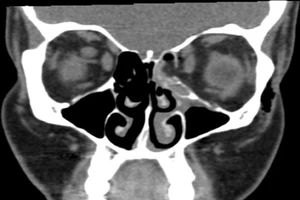

Gãy vụn xương hốc mắt vì hỉ mũi quá mạnh